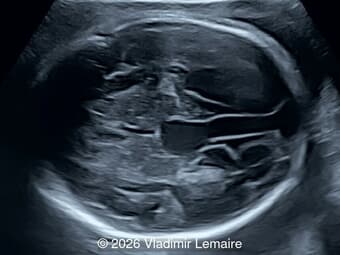

A 35-year-old secundigravida was referred to our unit at 20 weeks gestation for evaluation of suspected fetal skeletal abnormalities. Her first child was healthy, and her personal and family history were otherwise unremarkable. Two years later in a subsequent pregnancy, the patient presented for ultrasound evaluation. This examination was performed at 13 weeks of gestation and demonstrated the following findings: